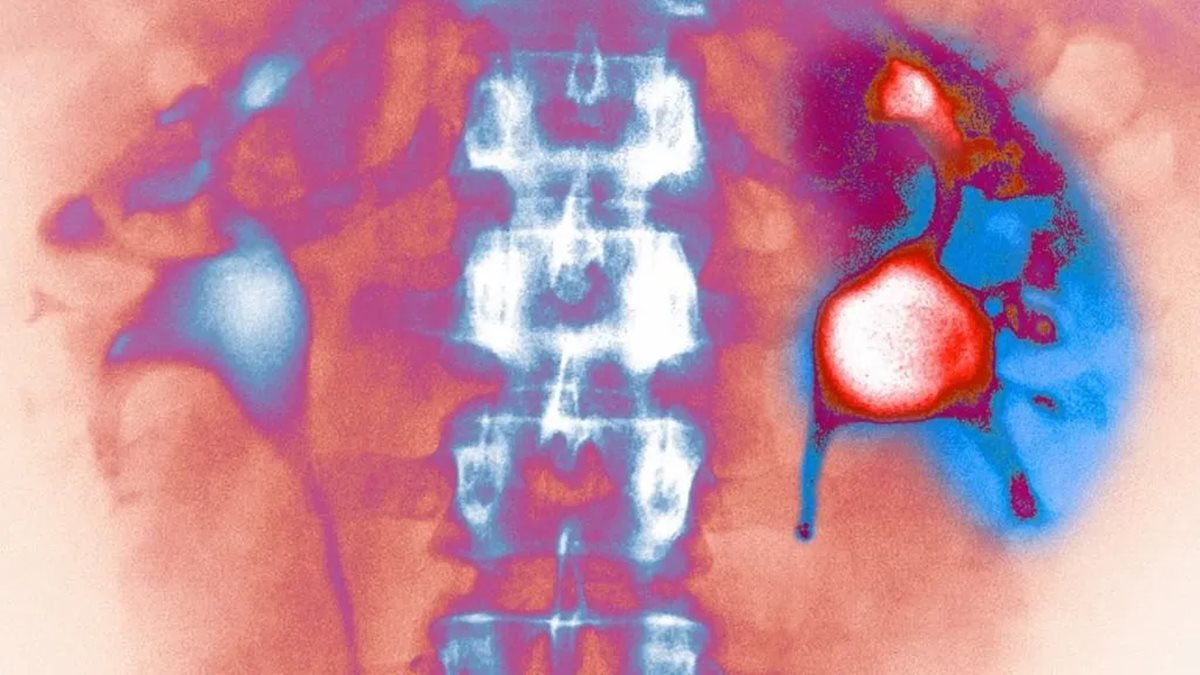

Évtizedek óta az orvosok egyetlen fő tanácsot adnak a vesekő megelőzésére: igyunk több vizet. A vízivás fontosságát senki sem vitatja, azonban a legújabb kutatások rávilágítanak arra, hogy ez önmagában nem elegendő a fájdalmas vesekövek kialakulásának megakadályozásához. A tudományos közösség most új irányokba tekint, és átfogóbb megoldásokat keres.

Charles Scales, a Vanderbilt Egyetem urológusa és kutatója, forradalmi megállapításokat tett közzé a témában. Scales professzor éveket töltött azzal, hogy megértse, miért térnek vissza a vesekövek még azoknál a betegeknél is, akik lelkiismeretesen követik az orvosi tanácsokat. Az eredmények megdöbbentőek: a puszta folyadékbevitel növelése csak egy része a megoldásnak, és sokkal összetettebb életmódbeli változtatásokra van szükség - írja az origo.hu

A vesekő kialakulása rendkívül összetett folyamat, amelyet számos tényező befolyásol. A The Lancet folyóiratban megjelent tanulmányok szerint a táplálkozási szokások, a só- és fehérjebevitel, valamint a kalciumpótlás időzítése mind kritikus szerepet játszanak. Következésképpen a megelőzés holisztikus megközelítést igényel, nem csupán a poharak számolását.

A kutatók felfedezték, hogy bizonyos élelmiszerek és italok – például a magas oxaláttartalmú zöldségek vagy a cukros üdítőitalok – jelentősen növelik a kockázatot. Ezért a szakemberek most arra ösztönzik a betegeket, hogy ne csak a folyadékmennyiségre, hanem annak minőségére is figyeljenek. A citrusfélék fogyasztása például kedvezően befolyásolhatja a vizelet összetételét, míg a túlzott húsfogyasztás fokozhatja a vesekő képződésének esélyét.